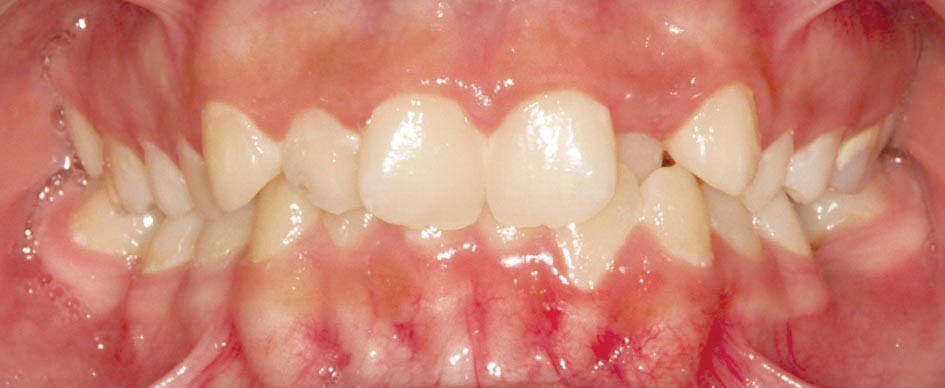

پس از برطرف شدن کرادینگ انسیزورها اگر باز هم Laceback محکم شود باعث جدا شدن کانین از لترال میگردد، لذا در این زمان Laceback را دیگر محکم نمیکنیم و باید سیم را ضخیم کنیم مگر در دو مورد: لترالهای کوچک یا Peg Shape برای اصلاح سایز دندان (شکل 16-3) و لترال پالاتالی که به همراه Off بودن میدلاین است (شکل 17-3).

شکل 16-3: لترالها با سایز کوچک

شکل 17-3: off بودن میدلاین به خاطر کرادینگ نا متقارن (لترال پالاتالی)